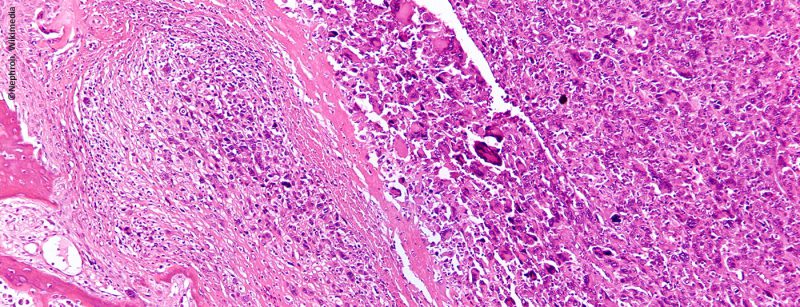

Behandlung von primären Knochentumoren am Becken

Chirurgische Resektion stellt den Hauptpfeiler der Therapie von Knochensarkomen des Beckens dar. Die Behandlung ist komplex und sollte individualisiert erfolgen. Durch Austausch von Daten und Expertenwissen kann die Erkrankung besser...…